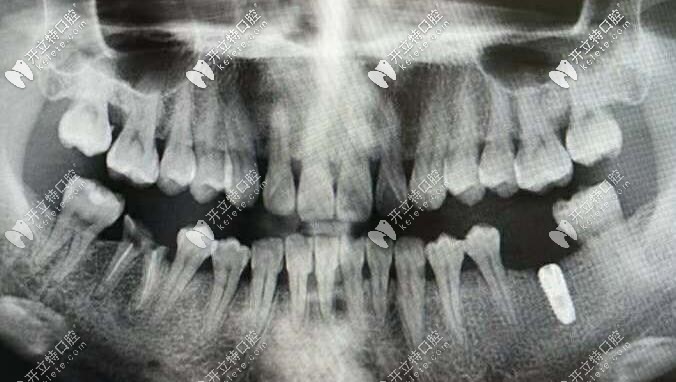

韓國inno種植體

伊諾種植系統(tǒng)

伊諾種植體外觀

伊諾種植體<span style=

伊諾種植體優(yōu)勢